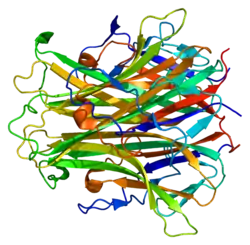

Osteopetrosis is caused by underlying mutations that interfere with the acidification of the osteoclast resorption pit, for example due to a deficiency of the carbonic anhydrase enzyme encoded by the CA2 gene.[12] Carbonic anhydrase is required by osteoclasts for proton production. Without this enzyme hydrogen ion pumping is inhibited and bone resorption by osteoclasts is defective, as an acidic environment is needed to dissociate calcium hydroxyapatite from the bone matrix. As bone resorption fails while bone formation continues, excessive bone is formed.[13]

The genes associated with osteopetrosis are involved in the formation, development, and function of specialized cells called osteoclasts. These cells break down bone tissue during bone remodeling, a normal process in which old bone is removed and new bone is created to replace it. Bones are constantly being remodeled, and the process is carefully controlled to ensure that bones stay strong and healthy.[14]

Mutations in any of the genes associated with osteopetrosis lead to abnormal or missing osteoclasts. Without functional osteoclasts, old bone is not broken down as new bone is formed. As a result, bones throughout the skeleton become unusually dense. The bones are also structurally abnormal, making them prone to fracture. These problems with bone remodeling underlie all of the major features of osteopetrosis.[14]